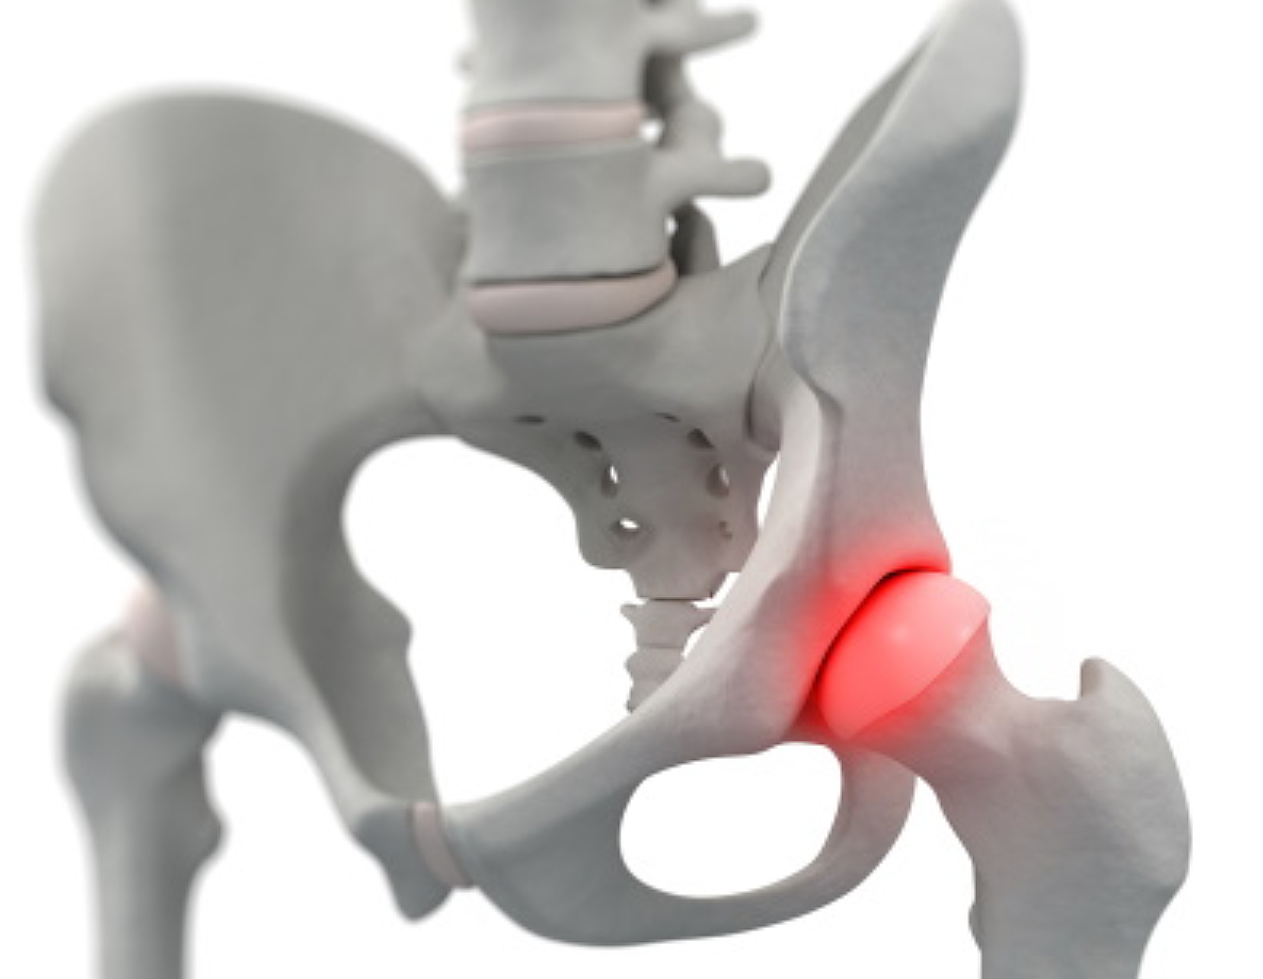

우리나라에서 발생하는 고관절 통증 증상의 가장 큰비중(70%)을 차지하는 대퇴골두 무혈성 괴사는특히 30~50대 젊은 남성에서 많이 발생하는 것으로 알려져 있습니다. 이 질환은 고관절의 기능을 완전히 잃게 할수 있어 주의가 필요합니다.

고관절은 골반 뼈 속에 공처럼 생긴 대퇴골의 골두가 맞물린 관절입니다. 대퇴골두는 다른 부위에 비해 혈액 순환 장애가 쉽게 올 수 있으며, 혈액 순환 장애는 대퇴골두 무혈성 괴사를 유발합니다. 뼈가 썩으면 몸의 하중을 정상적으로 견디지 못해 미세구조에 골절이 생기고, 심각한 통증이 발생합니다.

뚜렷한 원인은 밝혀지지 않았지만, 과다한 음주가 골 괴사의 위험을 높이는 가장 큰 원인입니다. 형외과 전문의는 “대퇴골두 무혈성 괴사는 여성보다는 남성에게서 많이 나타나고 환자의 60%는 양쪽 고관절 통증 증상에 모두 나타난다”며 “발병 요인 중 한국 남성들의 음주 습관이 큰 원인으로 꼽히고 있습니다. 자주 술을 마시게 되면 혈액에 콜레스테롤과 지방 등이 쌓이게 되고 이것이 혈관을 수축시키는데, 이때 혈압이 증가하고 혈액이 응고되면서 혈액 순환을 방해하게 됩니다. 과음으로 인해 급성으로 진행돼 고관절 뼈가 주저 앉는 사례도 있어 조기에 치료받는 것이 중요합니다.